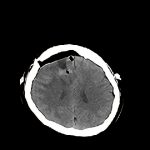

脳腫瘍

断層撮影

手術前1

手術後

No.’13_112 手術前1

No.’13_112 手術後